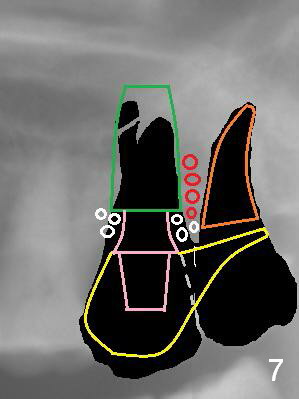

A 53-year-old woman has toothache in the upper left sextant. It appears that the teeth #15 and 16 are non-salvageable due to proximal root caries (Fig.1 *). The tooth #15 is extracted first and the socket will be packed with 2% Xylocaine, 1:50,000 Epinephrine gauze. The decay at #16 will be removed to reduce intraop contamination (Fig.3 *), followed by insertion of a piece of gauze (Fig.3 white). Rounded tapered (RT) osteotomes (Fig.3 red arrow) or drills will be used for sinus lift (Fig.1 ^: sinus floor). With the 3rd molar temporarily in site, the trajectory of the osteotomy is easily controlled.

Once an implant is placed at the site of #15, the tooth #16 is extracted (Fig.4). With a piece of gauze in the implant well, allograft/Osteogen is placed around the implant (Fig.5 red circle), while collagen plug in the socket of #16 (Fig.5 brown) if necessary. After removal of the gauze from the implant well, an abutment is placed (Fig.5 pink). More graft is placed around the implant shoulder (Fig.6 white circles). An immediate provisional at #15 could be extended distally to cover the #16 socket (Fig.7 yellow). Two weeks later the provisional is modified (Fig.7 grey dashed line) to remove the distal extension.